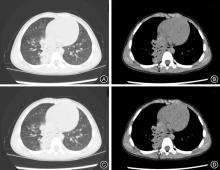

CLC Number:

Linmei HAN,Yingli REN,Yiman LI,Fen HUANG,Taoming. DU. Feasibility study of low⁃dose chest CT with deep learning reconstruction algorithm combined with axial scan in children with mycoplasma pneumoniae pneumonia[J]. The Journal of Practical Medicine, 2025, 41(21): 3428-3434.